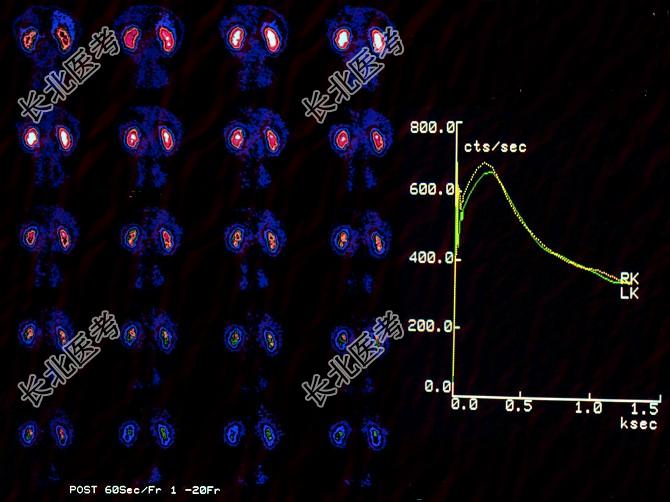

- 多项选择题一男性,45岁, 体检行

Tc

-DTPA肾动态显像如图,正确的诊断是 ( )

A、双肾动脉血流灌注正常

B、右侧尿路梗阻

C、双肾实质功能正常

D、右侧肾动脉狭窄

E、左侧肾动脉狭窄